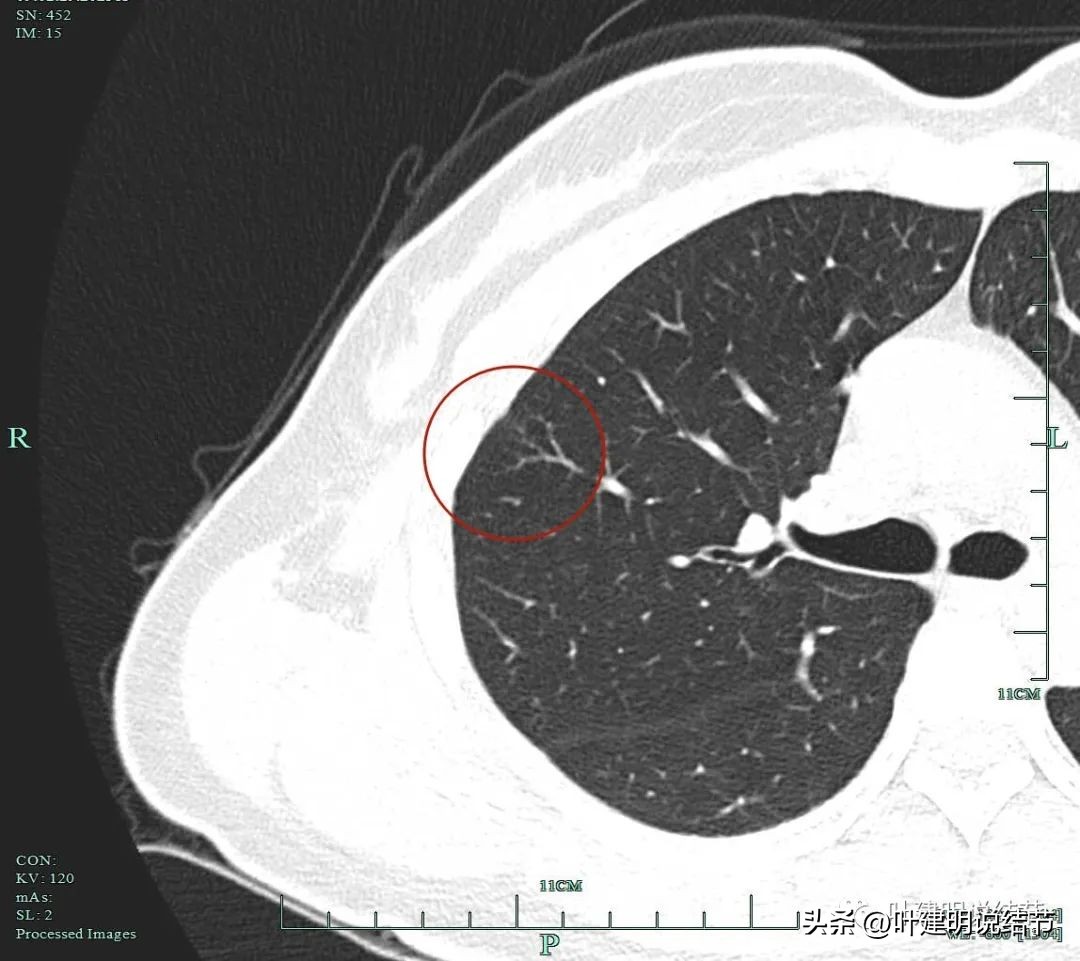

上图示病灶1的定位,红色箭头示病灶1,绿色箭头示定位医用胶。

上两图示病灶2的定位:红色箭头示病灶2,绿色箭头示医用胶。层厚1.25毫米,两者相差5层,也就是说上下相差6.25毫米,术中见到医用胶后,病灶在其下方6.25毫米。